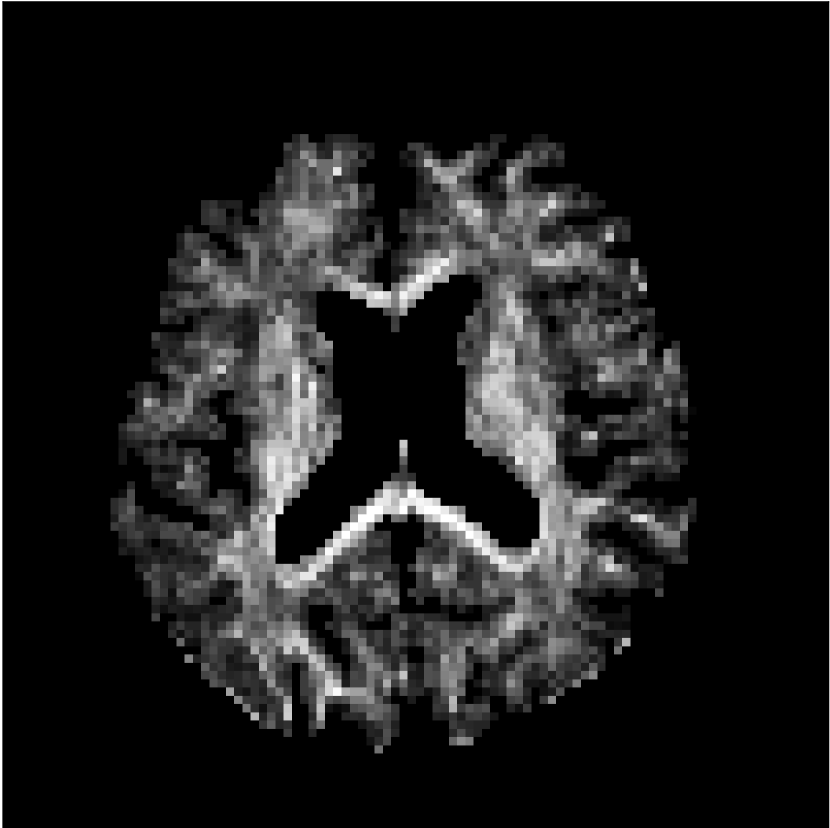

Figure 10 compares mean diffusivity maps across various partial Fourier factors between the CCNN and state-of-the-art methods.

No PF

7/8 PF

6/8 PF

5/8 PF

SoA

CCNN

MD, μ𝜇\mum2/ms

Figure 10: Comparison of mean diffusivity (MD) parameter maps across PF factors of 5/8ths, 6/8ths, 7/8ths, and without PF (No PF). The methods include state-of-the-art (SoA) and CCNN methods. Without partial Fourier, both methods are similar; however, as the PF factor increases, substantial artifacts are introduced in the SoA method, particularly around the lateral ventricles. The CCNN method is able to reduce the introduction of artifacts.

The methods perform similarly without partial Fourier acceleration, but as partial Fourier acceleration increases, the image is continually degraded in the SoA method, with "black voxels" appearing around the lateral ventricles. The CCNN method mitigates the appearance of these artifacts in the parameter maps.